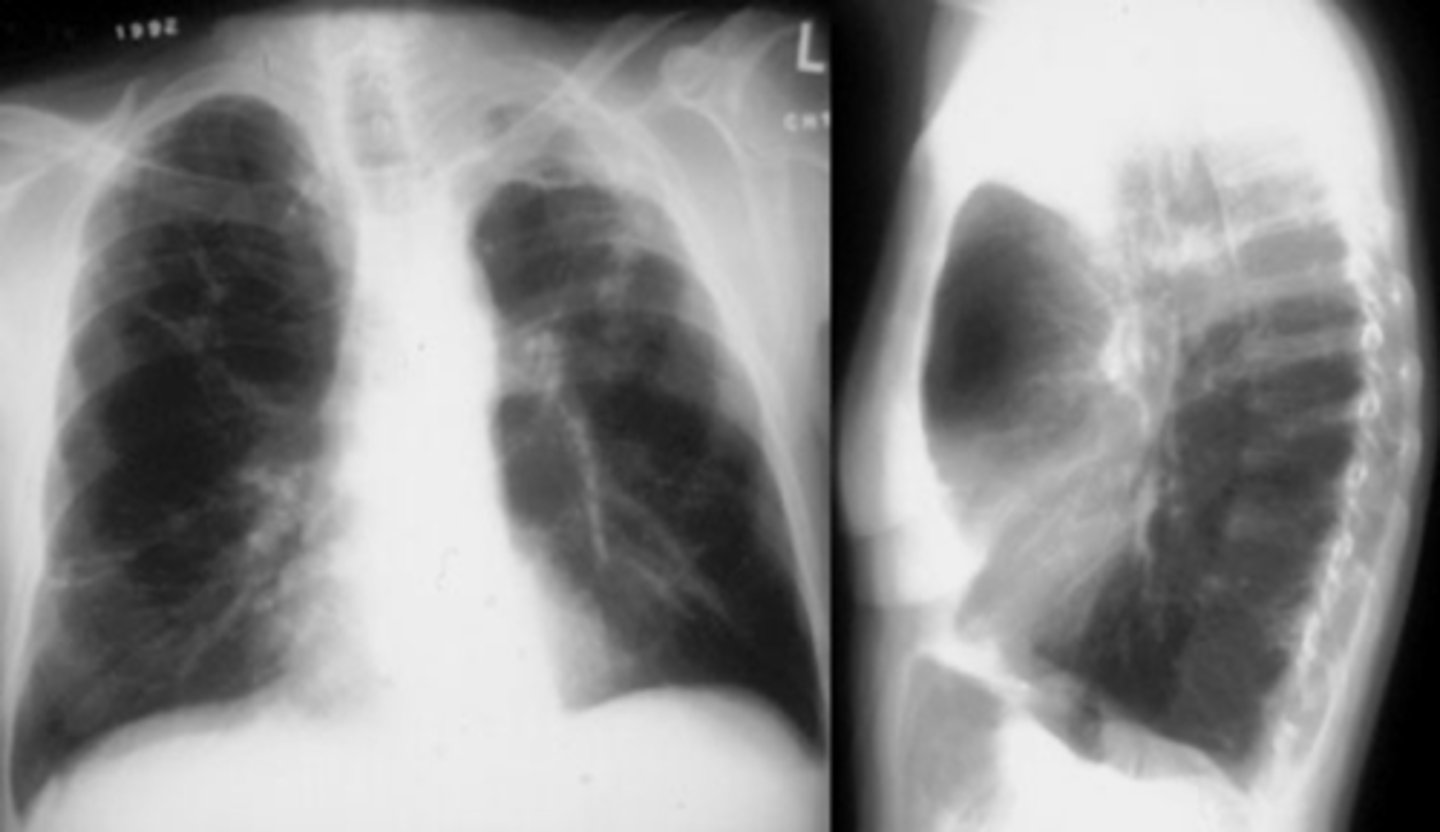

Flattening of hemidiaphragms

& blunting of costophrenic angles, Increased AP diameter (barrel chest), bullae or large air cavities indicates

hyperinflation

COPD/Emphysema

COPD/Emphysema